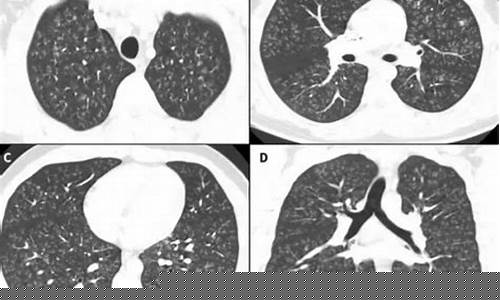

爆米花肺,医学上被称为“间质性肺病”,是由于长期吸入某些化学物质导致肺部损伤的病症。其得名源于早期与爆米花厂工人相关的案例。这些工人长期暴露在一种名为二乙基乙酰胺(diacetyl)的化学物质中,导致肺部出现纤维化和严重损害。近年来,电子烟中的某些成分,尤其是与香料相关的化学物质,也被发现可能会引发类似的肺部问题。

爆米花肺的主要症状包括持续的干咳、呼吸急促、胸部不适、疲劳等。随着病情的进展,患者可能会出现呼吸困难、肺部持续损伤,甚至导致肺功能衰竭。由于爆米花肺的症状与许多其他呼吸系统疾病相似,早期很难诊断。因此,如果长期使用电子烟并出现类似症状,应尽早就医。